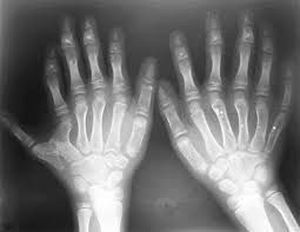

Polydactyly

Polydactyly is the growth of extra fingers and toes while ectrodactyly is the absence of fingers or toes.